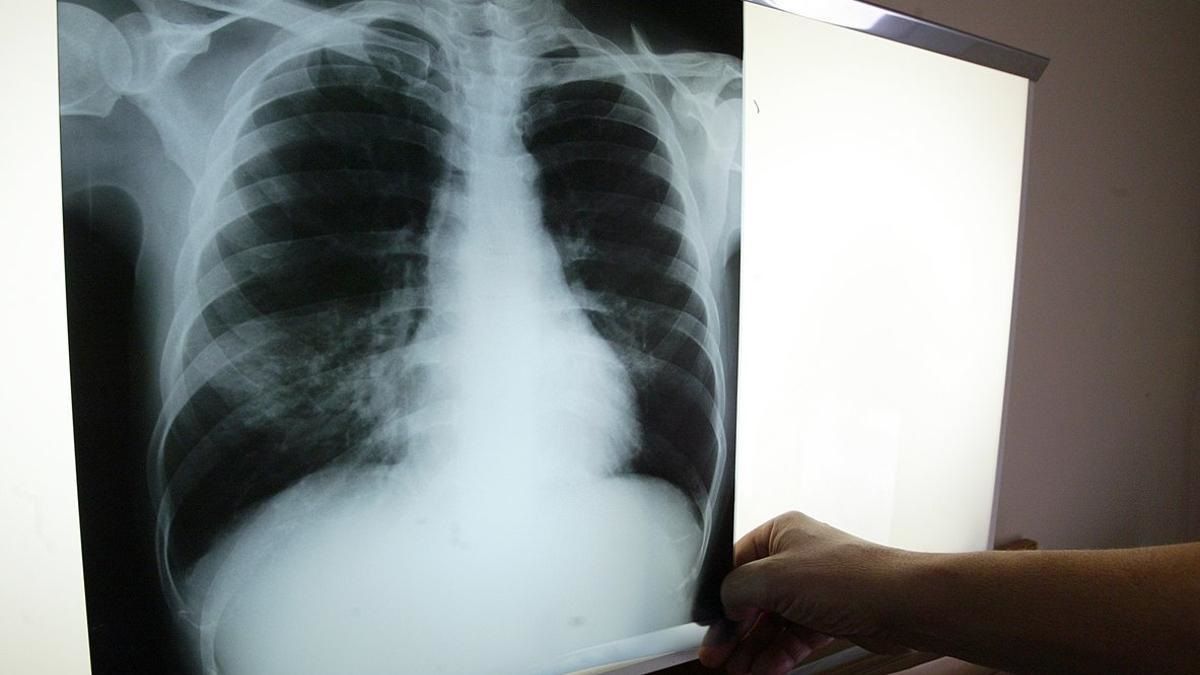

Para contextualizar, la tuberculosis es una enfermedad infecciosa causada por la bacteria Mycobacterium tuberculosis o bacilo de Koch, que afecta principalmente los pulmones, aunque puede comprometer otros órganos del cuerpo. Se transmite por el aire a través de las gotas microscópicas que expulsa una persona infectada al toser, lo que permite que otras personas sanas inhalen la bacteria.